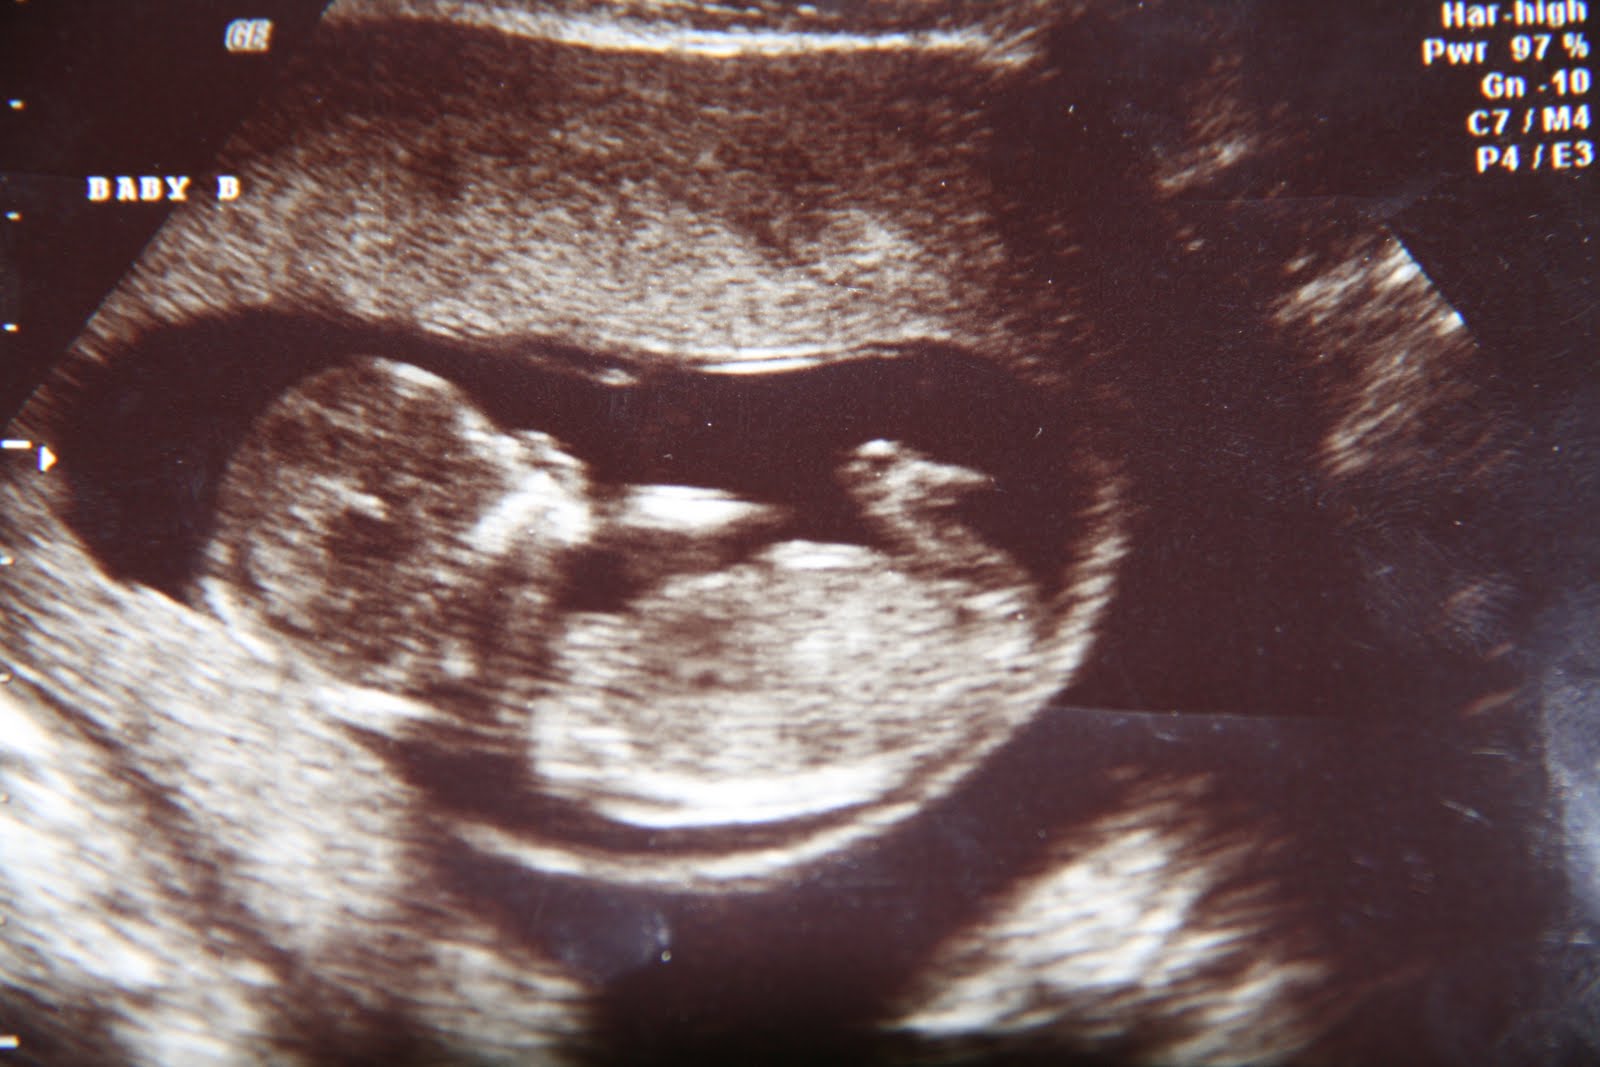

At our sonogram this morning the boys were measured. We were excited to hear that they both are at the 1 pound mark! Baby A is 1 lb 1 oz, and Baby B is 1 lb. Baby A still has no fluid, but his bladder is working well and producing fluid, and my doctor said she was very pleased with that, as well as their weight gain.

Ps- I hit my 5 mo mark last week, and remembered I needed a belly pic for this month! Also, today is the first time I could SEE movement on the outside of my tummy! And I pushed in a little on baby B, and he kicked or punched back! It's still surreal to me they are really inside me. I'm praying for many, many more moments like these. :)

Tomorrow we see the boys again and we get updated measurements of how they've grown in the last two weeks! We are also continuing to pray that some fluid shows up on the screen for baby A.

In December, we went back at 17 weeks and were going to find out the genders of the babies! We had a sneak peak at 13...so we know one was a boy for sure, but the other was hard to tell..although it also looked boy. But I wanted to hold out some hope for a girl so we just quietly waited until this appointment to know for sure. And so...TWO BOYS it was! WO! I wasn't sure if God was just really having a good ole laugh up there or not. I'm a pretty girly girl. But, I knew HE knew better than I did and knew what I needed. We were SO thankful to still have two healthy babies! I just decided I would completely spoil all my girl godchildren!! None of their moms protested. ;)

The next day she called with a positive test! And my hormone # was through the roof! A normal number for 4 weeks pregnant is 50-100. For twins, maybe around 200. Mine was 534! I was hoping to just be in the normal range and God wanted to bless with me with a number that was WAY more than normal or ok. She was actually concerned there could be more than 2 babies in there! We didn't care about that yet... we were just elated to have a strong number! Finally a pregnancy that was looking healthy. We were so excited, but still cautious...we had a long way to go still. But we praised God so much for His faithfulness so far!! (The picture above is of the two embryos we implanted!)